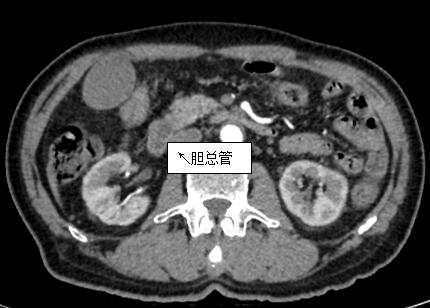

69歲王姓患者,因“發(fā)現(xiàn)無(wú)痛性黃疸1月”入院,根據(jù)患者病史,患者診斷傾向于壺腹部腫瘤所致梗阻性黃疸。予以完善腹部CT及上腹部MRI加MRCP均顯示肝內(nèi)外膽管擴(kuò)張,未發(fā)現(xiàn)明顯膽管,胰腺及十二指腸乳頭部腫瘤,且患者CA199正常。以前醫(yī)院未引進(jìn)超聲內(nèi)鏡,這類患者到此就遇到診斷瓶頸。此患者經(jīng)過消化內(nèi)科張丹霞副主任醫(yī)師完善超聲內(nèi)鏡檢查后,可以清楚顯示膽總管下段壁內(nèi)軟組織占位?;颊咄ㄟ^超聲內(nèi)鏡檢查診斷明確,轉(zhuǎn)至肝膽外科行手術(shù)治療。

上腹部CT圖片